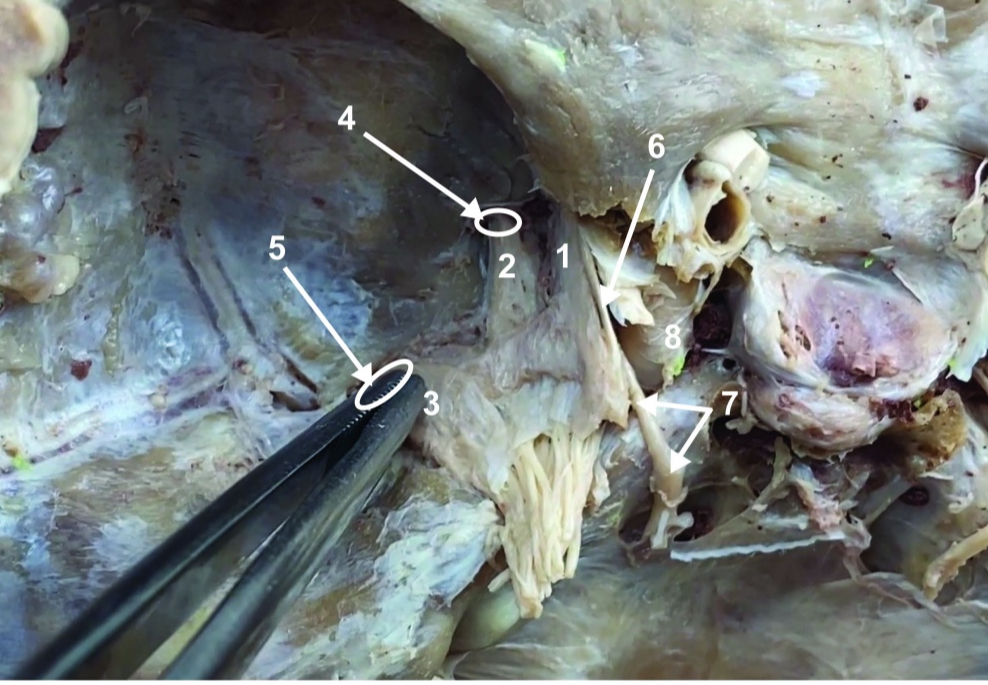

A. Identify structure

Transverse foramen; Vertebral a.

B. Identify structure; What goes through this feature?

Transverse process

C. Identify structure

ID structure

Spinal accessory n. (CN XI)

ID structure

Transverse cervical a.

ID structure

Levator scapulae

ID structure

Rhomboid minor

ID structure

Rhomboid major

ID structure

Rhomboids (reflected)

ID structure

Splenius capitis

ID structure

Splenius cervicis

ID structure

Longissimus

ID structure

Iliocostalis

ID structure

Semispinalis capitis